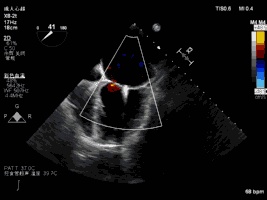

夹合术中(左房面观):三维心超示夹合后双孔征

夹合术中(左室面观):三维心超示夹合后双孔征